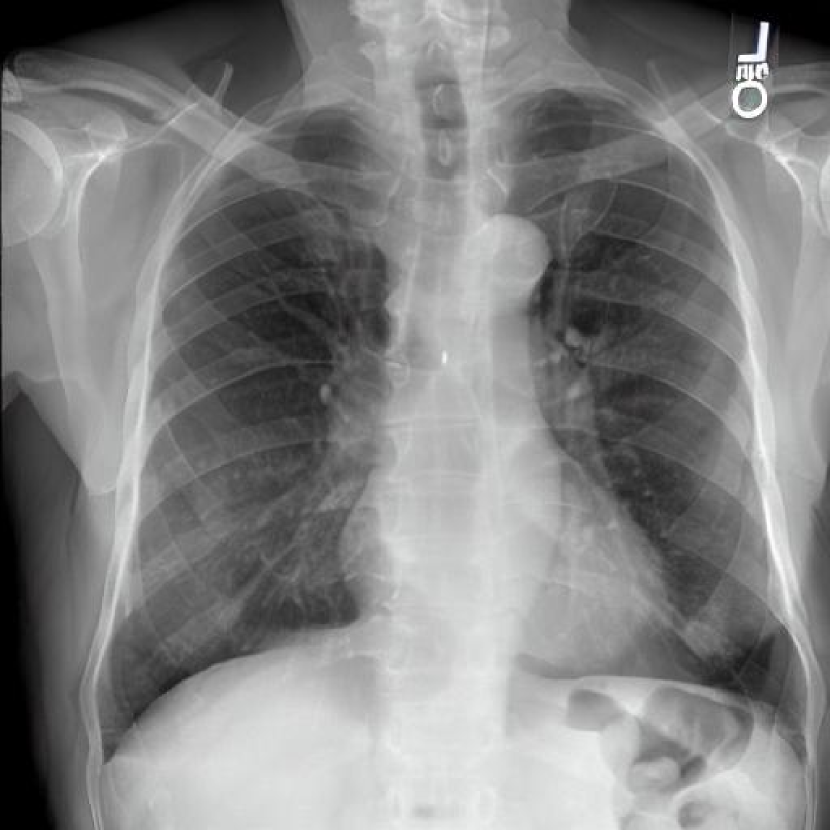

Leveraging Synthetic Data. With the advent of generative modelling tools, we are armed with the power to mitigate the problem of having a long-tail by supplementing the rare labels. We run a small experiment to evaluate whether we can use RoentGen [2], a prompt-based Stable Diffusion model to generate realistic chest X-rays and augment the training data. We generate about 5000 X-rays for training containing at least one pathology from the tail classes. We curate prompts for RoentGen by translating the Spanish reports available in the PadChest dataset to English, and also generate radiologist report-like prompts using ChatGPT 111chat.openai.com by providing curated templates. Figure 3 shows examples of prompts and the corresponding synthetic X-rays generated by RoentGen and verified by a radiologist.

Contribution of Synthetic Data. Figure 2 shows the increase in performance of the model over Table 1. This model was jointly finetuned on MIMIC CXR and a small synthetic dataset (refer Figure 3 for samples). Although the size of the synthetic dataset was too small for it to demonstrate an appreciable performance delta, these results show the promise of leveraging synthetic data to overcome the challenge of training on rare classes at least to some extent, especially since the biggest change is seen in the performance of the tail classes.